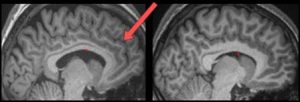

Among your memory’s biggest challenges is remembering what actually happened, versus what you imagined – that’s especially hard with some people I know. That ability, according to a new study, is linked to the presence of a small fold; even more interesting, some people have and some people don’t have this fold – a finding […]